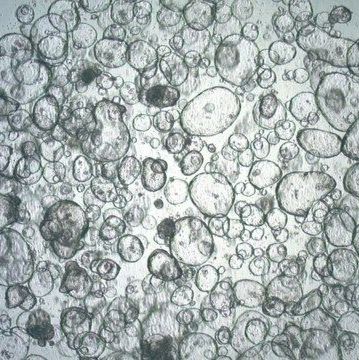

细胞名称:3dGRO Colon Intestinal Organoids, Age 59 (Prep ht-099-C)

规格:>1500 viable organoids/vial

应用:Organoid Growth: Pass

特点和优势:Cryopreserved patient derived gastrointestinal organoids (PDOs)

储存及稳定性:Store in liquid nitrogen. The organoids can be cultured for at least 10 passages after initial thawing without significantly affecting the cell marker expression and functionality.